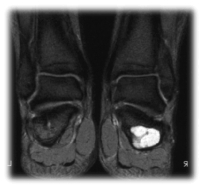

In the evolutionary radiological controls, a favorable but incomplete response was observed with a slight sclerosis of the lesion in the simple x-ray (Figure 3) and changes in the content of the cyst in the magnetic resonance (Figure 4A,4B).

Figure 4A. Sagittal T1 in which the treated lesion is seen, hypointense and already with morphological alterations of its content

Figure 4B. Coronal STIR. A large hyper signal continues to be observed in the fat suppression sequences